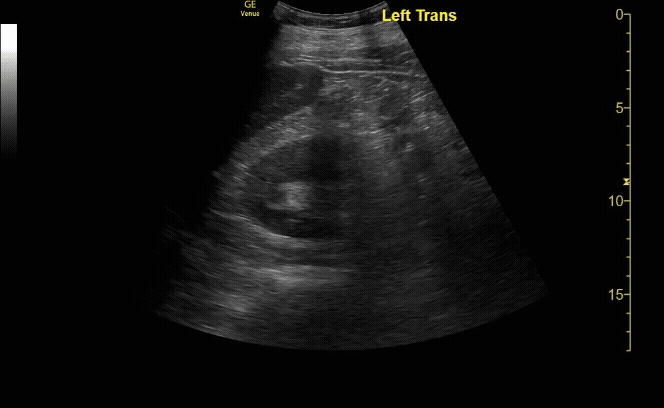

R/L kidney In transverse (short) view

c/o Victoria Gonzalez, MD